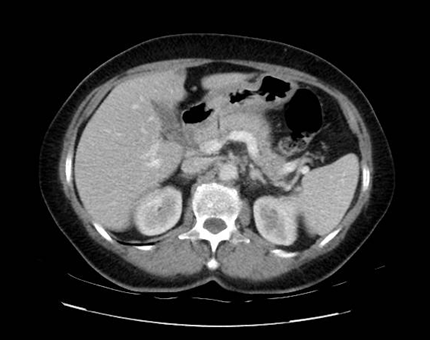

Se solicita Tomografía Computada de abdomen y pelvis (TC) con contraste intravenoso y vía oral (figura 1) que evidencia a destacar: estomago semidistendido, con imagen lineal de densidad baja que desde la pared del estómago se introduce en el páncreas, produciendo en la vena porta leve defecto de relleno en la pared, lo que podría corresponder a un cuerpo extraño. Adyacente al páncreas se observa leve alteración de la densidad de la grasa. El mismo presenta leve aumento de su tamaño de forma difusa. No líquido libre intraabdominal. Resto de órganos sin lesiones.

Figura 1: Tomografía de abdomen y pelvis. Evidencia imagen lineal de baja densidad que desde la pared del estómago se introduce en el páncreas y que produce en la porta un leve defecto de relleno en la pared.